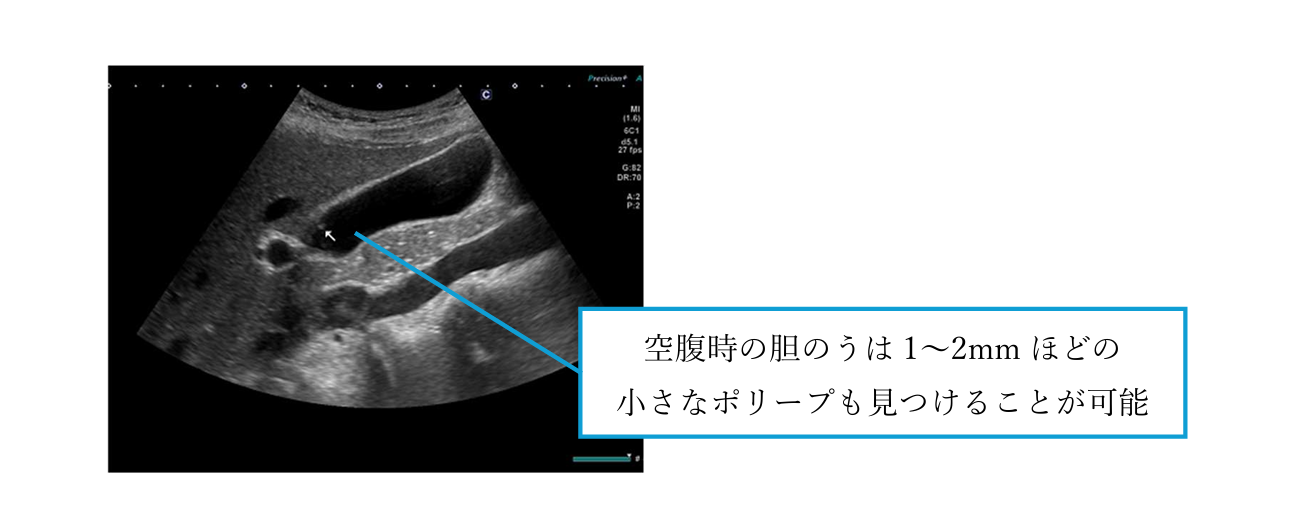

特殊光観察による微細病変の発見

当院では、オリンパス社製の内視鏡システム「EVIS X1」を導入しています。ハイビジョン画質での観察に加え、NBI(狭帯域光観察)などの特殊光を用いることで、通常光では見えにくい粘膜表面の微細な血管構造や、平坦で発見しにくい初期のがん・ポリープの発見に努めています。